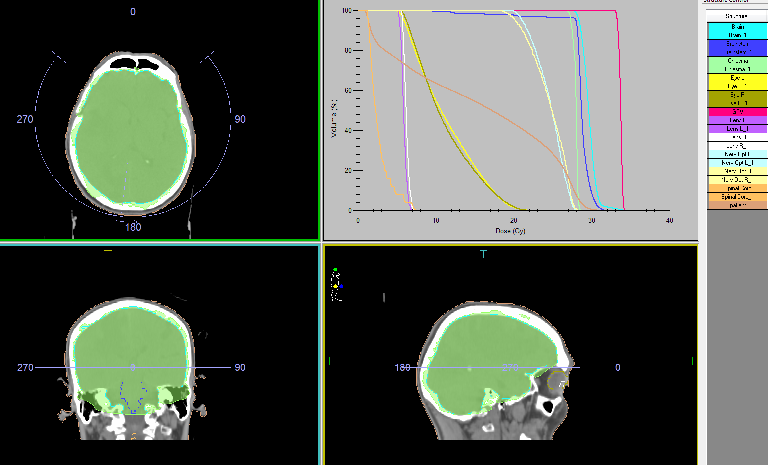

Intensity-modulated prophylactic whole-brain radiotherapy (WBRT) with daily dose (DD) 3 Gy up to total dose (TD) 30 Gy/ Biologically equivalent dose (BED) 38 Gy/5 times per week was performed (Figure 2).

Figure 2: The Intensity modulated prophylactic whole-brain radiotherapy (WBRT) with daily dose (DD) 3 Gy up to total dose (TD) 30 Gy.